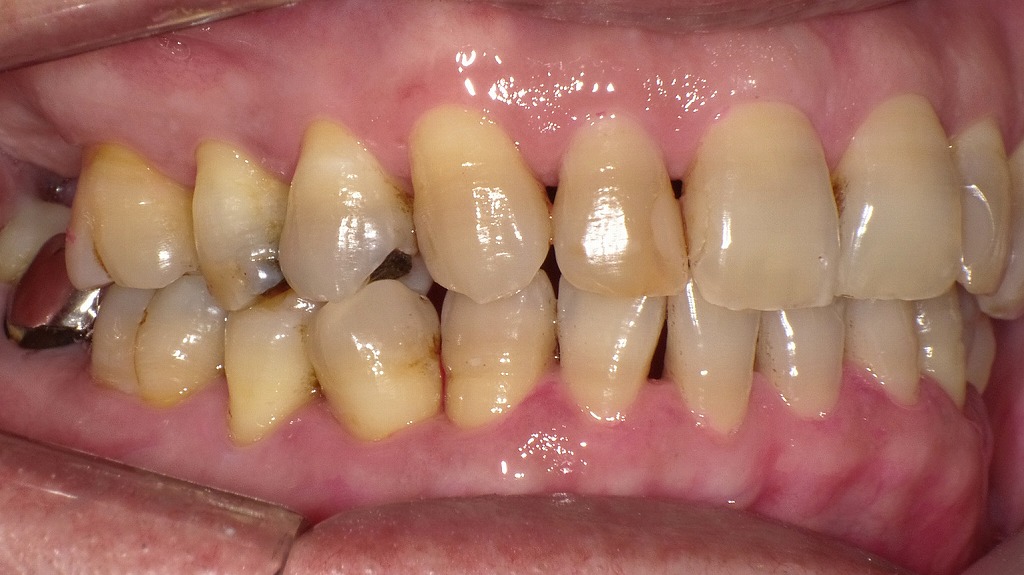

歯磨き不足によるプラーク残存による中等度歯周病の口腔内

歯磨きが不十分な状態では、歯面や歯間部にプラーク(歯垢)が多く残り、歯肉の炎症や出血、歯周ポケットの形成につながります。写真では、上下前歯部を中心に着色・歯垢の付着が認められ、歯肉の軽度腫脹も見られるなど、歯周病リスクが高い口腔内所見を示しています。適切なブラッシング指導と定期的なクリーニングが重要です。

この画像は、右側を中心に撮影された口腔内写真です。歯の表面や歯と歯ぐきの境目に、汚れや沈着物が多く見られます。以下のように分類して解説します。

🔹1. ステイン(着色)

矢印で示されている「ステイン」は、コーヒー・紅茶・タバコのヤニなどによる表面の着色汚れです。

歯の表面に付着しているだけなので、**歯科医院でのクリーニング(PMTCやエアフロー)**で比較的簡単に除去できます。

🔹2. 歯垢(プラーク)

中央部の「歯垢」は、**細菌のかたまり(バイオフィルム)**で、白っぽいまたは黄白色をしています。

歯ブラシが届きにくい歯と歯ぐきの境目に溜まりやすく、放置すると歯石に変化します。

歯垢が残ると、歯肉炎や歯周病の原因になります。

🔹3. 歯石

右側に示されている「歯石」は、歯垢が唾液中のカルシウムと結合して石灰化した硬い沈着物です。

表面がザラついており、さらに新しい歯垢が付きやすくなるため、歯周病を悪化させる原因になります。

自分では除去できないため、**歯科医院でのスケーリング(歯石取り)**が必要です。

🔹4. タバコのヤニの影響

歯の全体に茶褐色のヤニの沈着が見られます。

ヤニは歯垢や歯石の付着を助長し、歯ぐきの血流を悪化させるため、歯周病を進行させやすい要因です。

🔹5. 歯周病の進行状況

歯ぐきがやや下がり、歯と歯の間が広がって見えます。

また、歯石の沈着量や歯ぐきの炎症の程度から判断すると、**中等度の歯周病(歯周炎)**が疑われます。

歯を支える骨が部分的に吸収している可能性もあります。

🔹まとめ

この状態は、

- 歯石・歯垢の除去(スケーリング)

- 着色除去(エアフロー)

- 禁煙やブラッシング指導

を行うことで改善可能です。

ただし、すでに歯周病が進行している場合は、歯周外科などの歯周治療が必要になります。